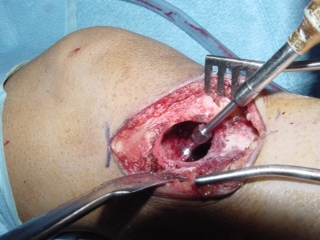

Gross (Fig. 8)

• Dependent on amount of lipid, fibrous tissue, and hemorrhage

• May be gray, yellow, white, or red

• Soft or firm

Fig. 8: Gross Pathology of a benign fibrous histiocytoma demonstrates multiple pieces of grayish fibrous tissue.

• Curettage (Fig. 10 & 11)

• Usually initial treatment

• Adjuvant therapy is recommended to reduce the recurrence rate. Cryotherapy for benign aggressive tumors has excellent results reducing the recurrence rate to approximately 3 to 5 %.